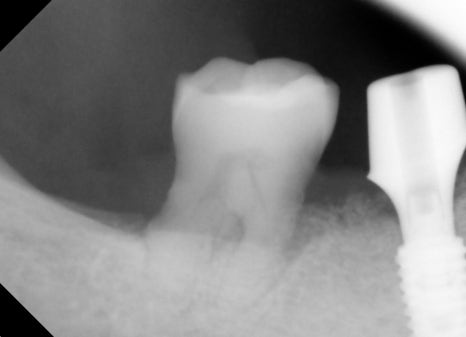

Prosthetic Treatment and the Final Steps

The final stage of implant treatment is the prosthesis.

The prosthesis is

The part that functions as the actual tooth,

and it is made to match the patient’s bite and shape.

In this case,

a custom abutment and a zirconia crown were used.

Molar implants are under strong chewing force in particular,

so bite adjustment is very important.

At the implant dental clinic, stability is ensured by checking the bite multiple times. Implant price can also vary depending on

the precision of the prosthesis.